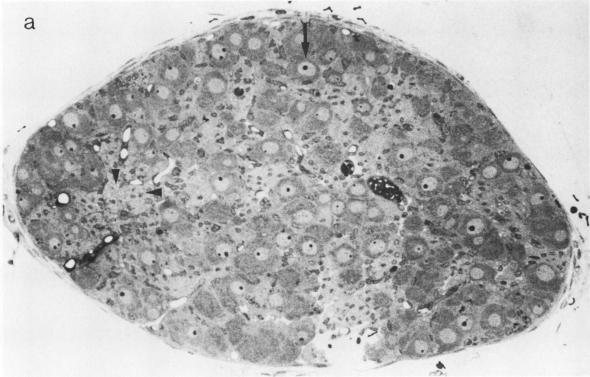

These studies have been undertaken to evaluate the role of the brain noradrenergic and dopaminergic pathways in the regulation of the secretion of thyrotropin-releasing hormone (TRH) in the central nervous system (CNS) and pancreas of the neonatal rat. When CNS stores of norepinephrine (NE) were selectively reduced by the subcutaneous administration of the dopamine-beta-hydroxylase inhibitor FLA-63, TRH concentrations were significantly reduced throughout the brain. However, when CNS stores of both NE and dopamine (DA) were depleted by the subcutaneous administration of the tyrosine hydroxylase inhibitor alpha-methyl-rho-tyrosine (alpha-MT), TRH concentrations in the brain were not significantly altered.FLA-63 and alpha-MT did not significantly reduce pancreatic catecholamine concentrations, indicating that in the basal state, these agents predominantly deplete central catecholamine stores. Nevertheless, pancreatic TRH concentrations were markedly reduced by FLA-63, and this effect was significantly attenuated by the simultaneous intracerebroventricular (icv) administration of NE. In contrast to the effects of FLA-63, alpha-MT caused a significant increase in pancreatic TRH concentrations, and this effect was significantly lessened by icv DA. To determine whether the sympathetic nervous system might be one route by which these central effects are mediated, a chemical sympathectomy was induced with guanethidine. This treatment selectively reduced pancreatic concentrations of NE, and caused a marked increase in pancreatic TRH concentrations. FROM THESE OBSERVATIONS, WE CONCLUDE THE FOLLOWING: (a) within the central nervous system, both NE and DA are involved in regulating brain TRH secretion or biosynthesis, and the direction of action of these two neurotransmitters appears to be opposite; (b) pancreatic TRH secretion or biosynthesis is also controlled by the brain noradrenergic and dopaminergic systems, and the net effects of each of these pathways appears to be opposite; (c) at least one route by which impulses from the brain may travel and modulate pancreatic TRH secretion or biosynthesis is by the sympathetic nervous system.